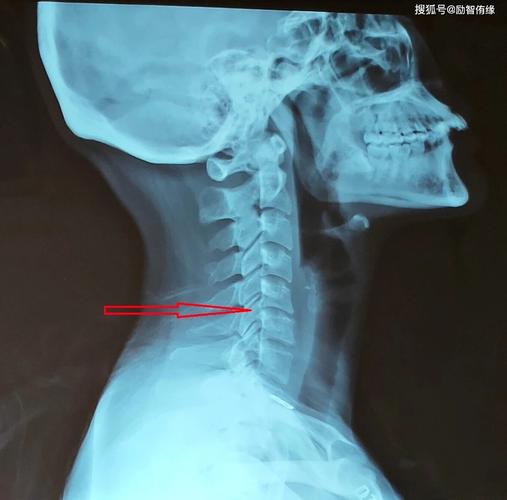

中医王财喜健康分享~不是所有肩痛都是肩周炎!_椎间盘